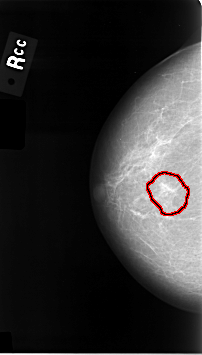

C_0014_1.RIGHT_CC

RIGHT_CC LINES 4608 PIXELS_PER_LINE 2624 BITS_PER_PIXEL 12 RESOLUTION 50 OVERLAY

FILE: C_0014_1.RIGHT_CC.OVERLAY

TOTAL_ABNORMALITIES 1

ABNORMALITY 1

LESION_TYPE MASS SHAPE IRREGULAR MARGINS ILL_DEFINED

ASSESSMENT 5

SUBTLETY 4

PATHOLOGY MALIGNANT

TOTAL_OUTLINES 1

BOUNDARY